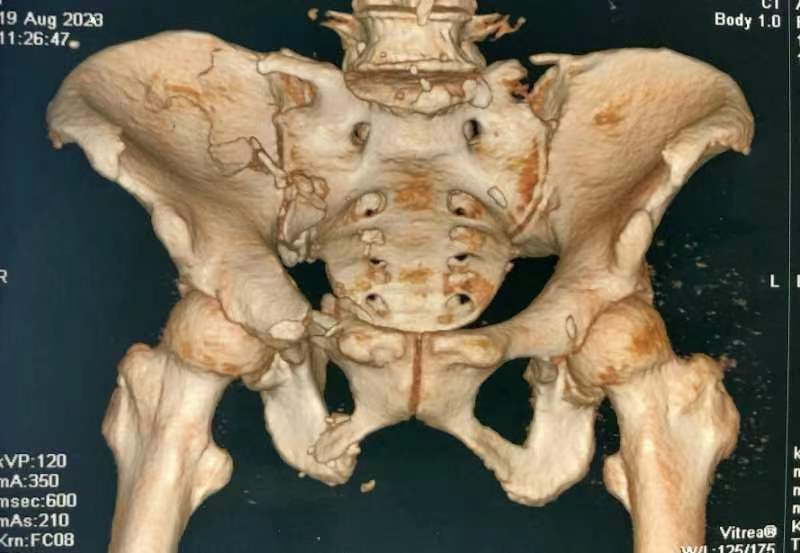

近日,MILAN.COM骨一科收治一位69岁骨折患者。患者遭遇车祸骨盆骨折、前后环损伤,造成骨盆旋转、垂直不稳定,导致翻身疼痛并且护理困难。

由于患者骨盆旋转和垂直不稳定,以及严重失血和肥胖,骨一科医疗团队进行讨论分析,决定采用微创内固定手术。8月25日成功完成手术,术后第二天患者能够在床上半靠,翻身时疼痛明显缓解,下肢功能恢复良好。